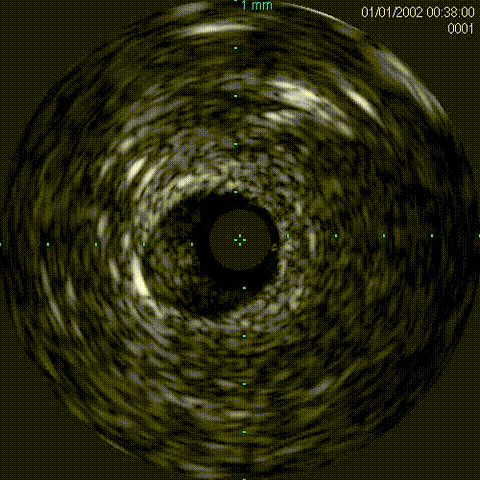

1、IVUS评估;

IVUS导管

Telescope™导引延长导管支撑,IVUS导管顺利通过

此病例为外膜钙化扭曲病变,超声导管无法通过,2.0mm小球囊通过困难,选用导引延长导管可以提高通过性,Telescope™导引延长导管在该病变中使球囊及IVUS导管通过顺利,器械输送效果及兼容性佳!

对于钙化病变,IVUS的选择还是必要的。如伴有钙化小结、环形钙化等,旋磨是一个好的选择,此病例无钙化小结及环形钙化,球囊扩张完全,所以未选择旋磨术。